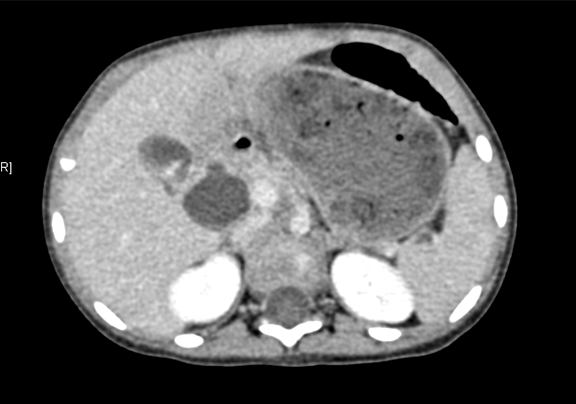

上腹部增强CT:符合先天性胆管扩张(胆总管)。

将0.625mm双源薄层CT资料的静脉期和动脉期Dicom格式文件导入海信CAS系统。

通过调节窗宽窗位调整CT序号,对肝实质,胆囊,胆总管,下腔静脉,肝动脉、门静脉及肝静脉等进行三维重建;系统自动计算肝脏体积。

术前CT检查:

动脉期

静脉期

平衡期